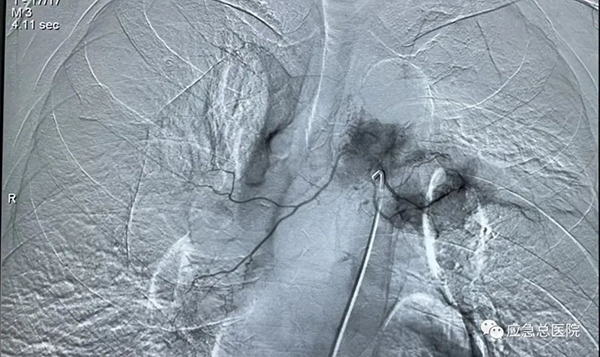

(3)经血管介入技术:常规开展支气管动脉灌注化疗、支气管动脉栓塞及血管内支架技术,应用于肺癌及咯血患者治疗,疗效确切。

气管镜下支架置入手术可以用于食道癌、肺癌、甲状腺癌等各种肿瘤引起的气道狭窄;其他疾病所致的气管、支气管瘘等良性气道狭窄。可以有效缓解患者气急、胸闷等呼吸困难症状,从而提高患者的生活质量,并为后续治疗提供宝贵机会。与外科手术相比,气管镜下支架置入技术具有不开刀、创伤小、操作简便、安全性高、术后恢复快、并发症少等显著优点。对于无法手术及无法耐受手术的恶性肿瘤患者,该方法创伤小,出血少,病人耐受性较好,可缓解症状,达到姑息治疗的目的。